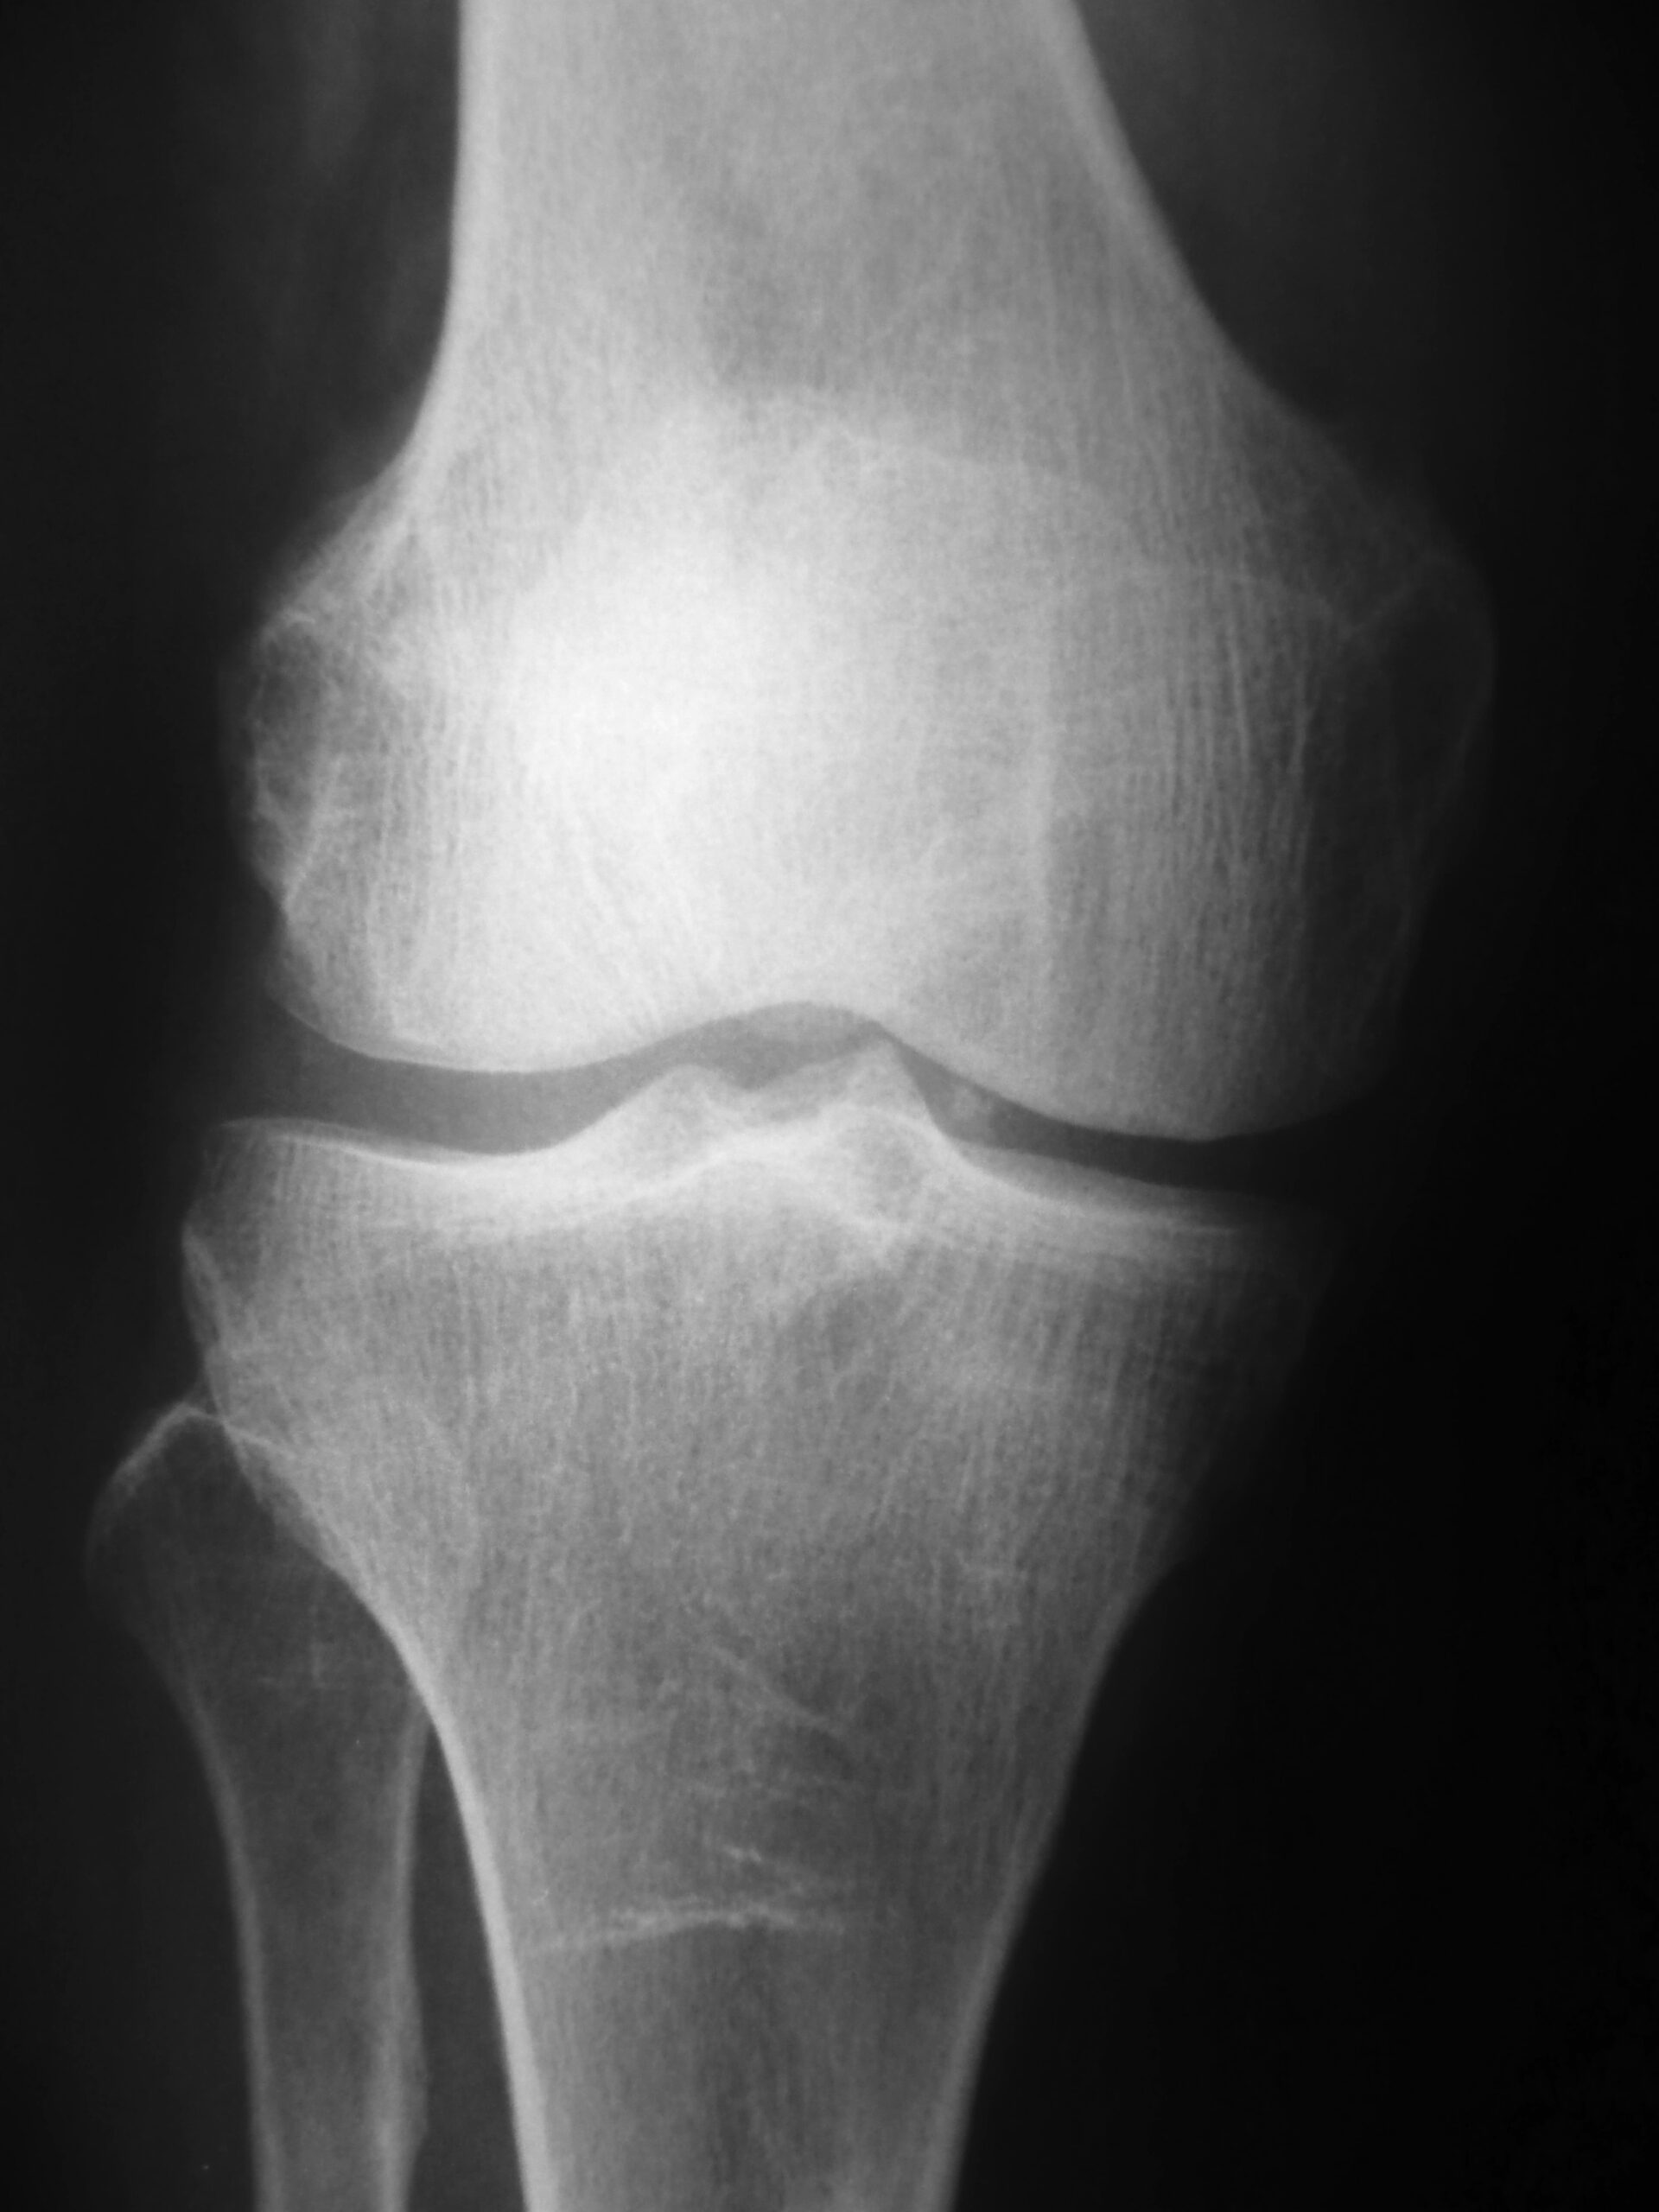

So you have been told you have knee arthritis, so what? If you have enough birthdays, you will have arthritis in some joint or another. Arthritis is just normal aging of the joints. Yet, the common belief is that arthritis is something to be feared. Something that is going to prevent a person from living an active life. People are told arthritis is the worst ever, that they will not be able to do things again, and that surgery is necessary.

What we know is that arthritis is normal aging. If we live long enough, we will get it. But we also know that there are millions of individuals walking around right now with knee arthritis and are just fine. They have no pain and are not limited in their physical activity in any way whatsoever. So, what this means is that not all individuals with arthritis are destined to the same outcome. Why? There is no one exact answer, BUT an attitude of positivity is important. This, along with taking an active approach to life.